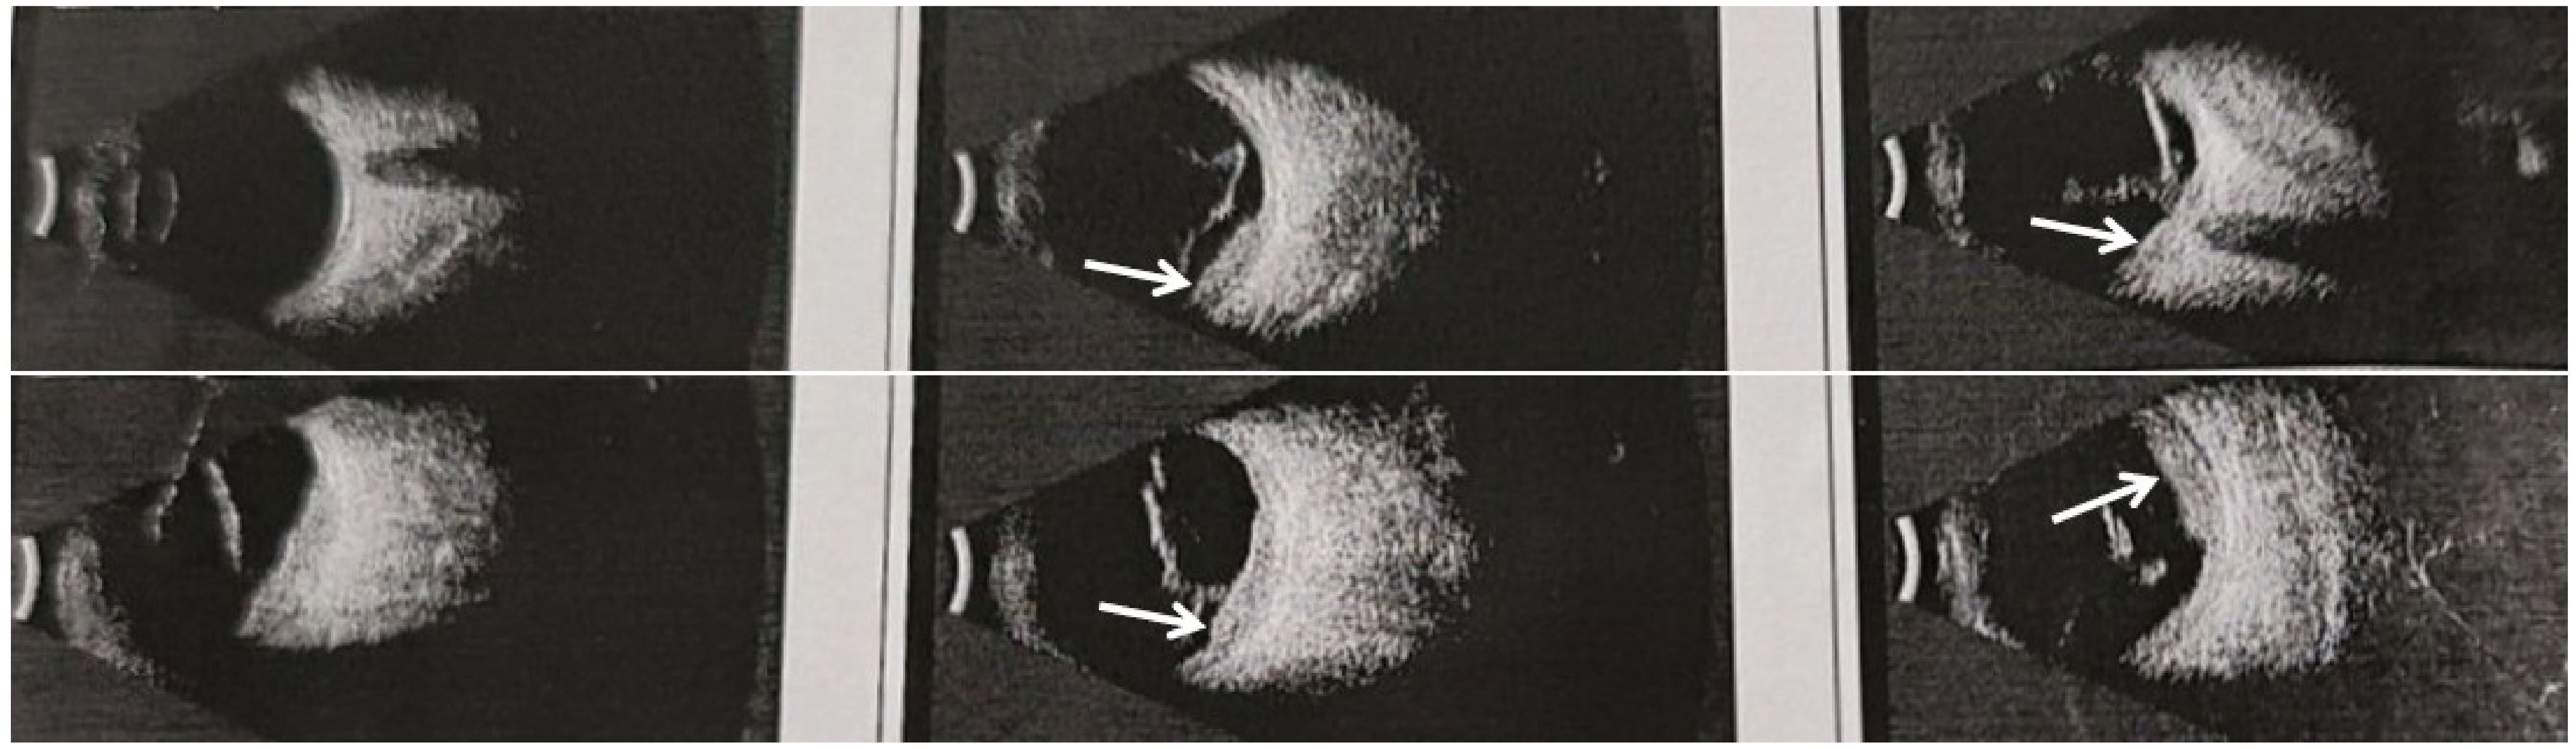

Background: Isolated ocular metastasis from esophagogastric junction (EGJ) cancer is extremely rare, and no standardized therapeutic approach has been established to date. Reporting such cases may help clarify optimal management strategies for uncommon metastatic patterns. Case presentation: We describe a 44-year-old male who developed isolated ocular oligometastasis ten months after radical EGJ cancer resection. Comprehensive evaluation confirmed left-eye involvement. Following multidisciplinary team (MDT) discussion, a combined treatment plan was implemented, starting with systemic therapy consisting of docetaxel, tegafur–gimeracil–oteracil (S-1), and tislelizumab. After achieving disease stabilization, the patient underwent left-eye enucleation with ocular prosthesis implantation, followed by adjuvant radiotherapy and maintenance S-1 chemotherapy. At a 55-month follow-up, he remains disease-free with an excellent performance status (PS 0). Conclusion: This case highlights that integrated multimodal therapy—including systemic and local interventions—can result in long-term survival for patients with isolated ocular metastasis from EGJ cancer. MDT-based, individualized treatment planning is essential for optimizing outcomes in rare metastatic scenarios and may inform future precision oncology approaches.